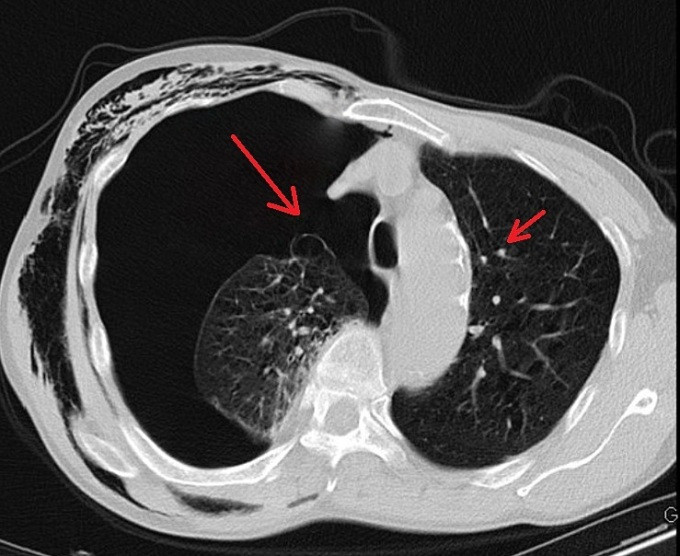

Sau hai ngày điều trị tại khoa Ngoại tổng hợp, tình trạng của ông K. không cải thiện, các bác sĩ chỉ định chụp CT ngực, phát hiện có nhiều kén khí rải rác ở hai bên đỉnh phổi và đáy phổi phải.

Các bác sĩ nhận định đây là trường hợp tràn khí màng phổi do vỡ kén khí, cần phẫu thuật nội soi. Điều này giúp bệnh nhân cải thiện chức năng hô hấp, vận động; tránh các nguy cơ khó thở kéo dài, tràn dịch màng phổi, áp-xe phổi, viêm mủ màng phổi.